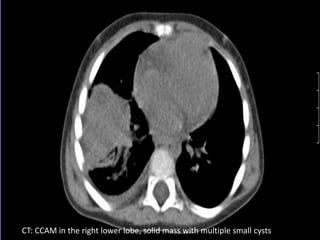

CT: CCAM in the right lower lobe, solid mass with multiple small cysts

CCAM • CT helpsin confirming the diagnosis, characterization of the lesion, and to document the involved lobe or segment • Intravenous contrast media must be used to define the presence of any systemic arterial vessels supplying the lesion • CT also helps to diagnose other associated congenital malformations

CT: CCAM inthe right lower lobe, solid mass with multiple small cysts